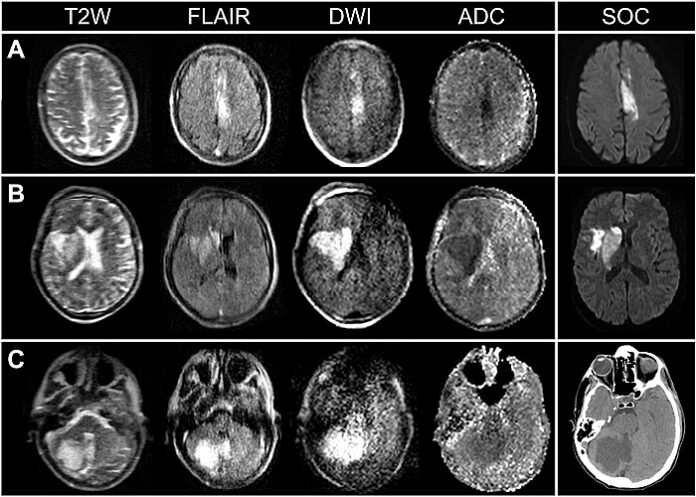

Brain imaging is essential to the clinical management of patients with ischaemic stroke. Timely and accessible neuroimaging, however, can be limited in clinical stroke pathways. Here, portable magnetic resonance imaging (pMRI) acquired at very low magnetic field strength (0.064 T) is used to obtain actionable bedside neuroimaging for 50 confirmed patients with ischaemic stroke. Low-field pMRI detected infarcts in 45 (90%) patients across cortical, subcortical, and cerebellar structures.

Lesions as small as 4 mm were captured. Infarcts appeared as hyperintense regions on T2-weighted, fluid-attenuated inversion recovery and diffusion-weighted imaging sequences. Stroke volume measurements were consistent across pMRI sequences and between low-field pMRI and conventional high-field MRI studies. Low-field pMRI stroke volumes significantly correlated with stroke severity and functional outcome at discharge.